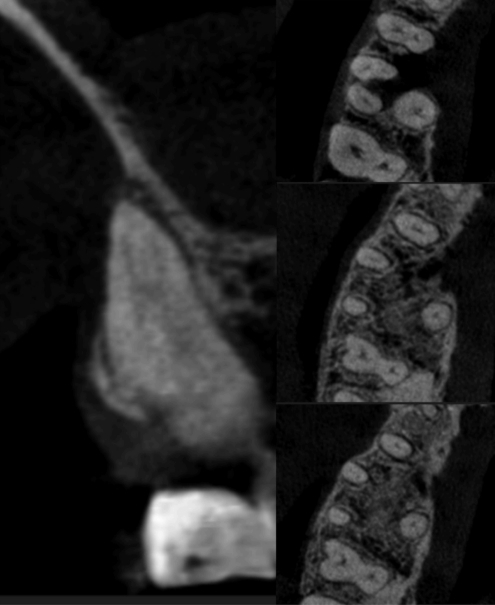

Рисунок 4 — Тип IV (34,9%)

Рисунки 4–6 представляют корональные и аксиальные срезы КЛКТ для трех наиболее часто встречающихся типов анатомических конфигураций.